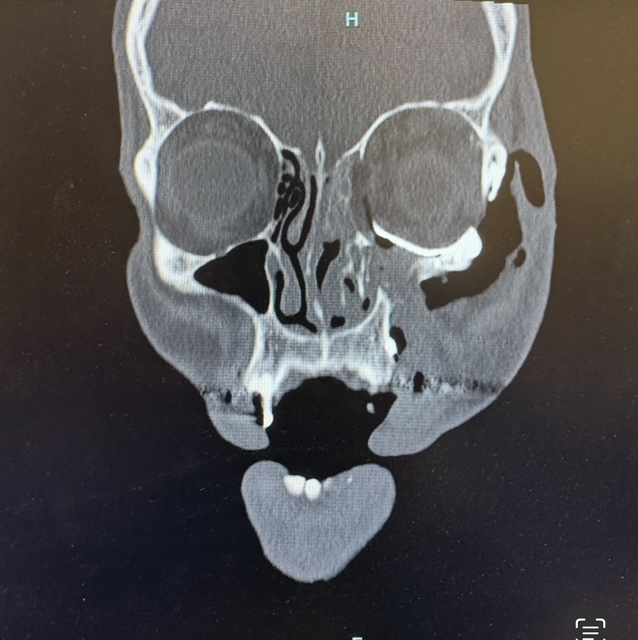

A young male patient presented to Hackensack University Medical Center after sustaining facial injuries subsequent to physical assault. As part of our NJ/NY hospital affiliations, Dr. Feuerstein and team were called to evaluate and treat the case. Imaging confirmed a left Zygomaticomaxillary Complex (ZMC) fracture and a left orbital floor fracture. These injuries affected midface projection, cheekbone position, and the structural support beneath the left eye. Without surgical repair, the patient risked:

Before addressing each fracture individually, the surgical team created a comprehensive plan to restore the patent’s facial symmetry, orbital support, and midface structure. Every step was aligned with the virtual model developed prior to surgery.

Post-Operative Outcome and Recovery

The patient recovered well following surgery. Facial projection, symmetry, and functional stability were restored – along with support for the left eye. This case reflects the depth of training oral and maxillofacial surgeons undergo. Beyond wisdom teeth and dental implants, Bergen Oral & Maxillofacial surgeons are extensively trained in: